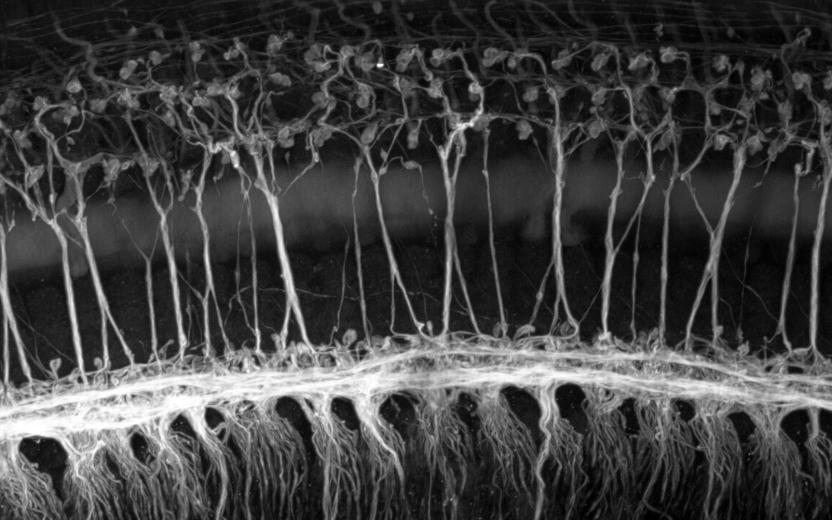

We study the physiology and molecular anatomy that underlie sound information processing in the auditory pathway. We study the pathophysiological mechanisms behind hearing loss. We aim to toward hearing restoration.